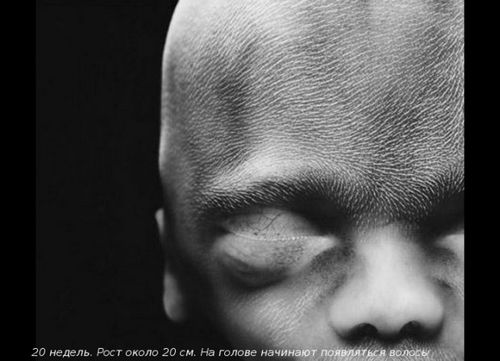

До 20-му тижні вагітності плід виріс до 25 см, виглядає як великий банан. Плід вже повністю сформований, а його тонка шкіра не настільки прозора.

У цей період відбувається знакова подія - дитина почує свою маму - биття її серця, дихання, голос (його окостенілі слухові кісточки тепер здатні проводити звуки). Малюк смокче пальчик, стає більш енергійним.

У кишечнику утворюється первородний кал - меконій і запускаються нирки. На очках чітко видно повіки і вії.